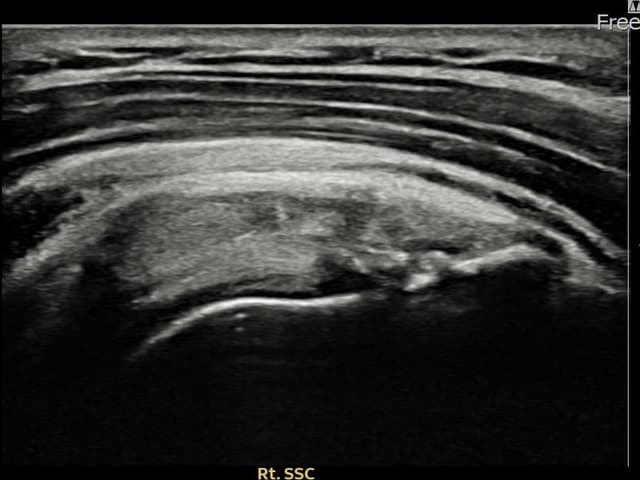

[촬영시기:23.12.14~24.02.22]

[어깨인대 축소봉합술] 우측 어깨 후방 통증과 외회전 시 심한 통증으로 내원하셨습니다.